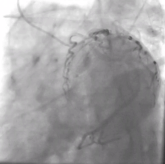

Introduction: An angiographic finding known as “coronary slow flow phenomenon” (CSFP) occurs when there is no discernible stenosis but the contrast flow is slower than usual. Although the prognosis for the majority of CSFP cases is favorable, frequent angina significantly lowers their quality of life. Therefore, this study aimed to explore the potential contributing risk factors and prognostic implications of CSFP on long-term cardiovascular outcomes.

Methods: This retrospective, cohort study was conducted between years 2014-2022 and included a total of 65 CSFP patients and 65 controls with normal coronary flow, as evidenced by coronary angiography. These two groups were examined in terms of future cardiovascular consequences due to this phenomenon, baseline demographic characteristics, and laboratory findings. A P value<0.05 was considered significant.